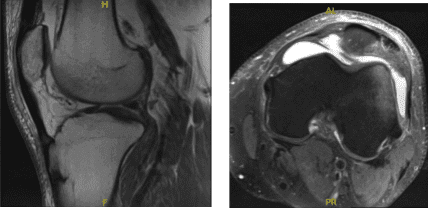

A result for MRI was presented and shown mildly displaced patellar fracture with accompanying longitudinal tear of the distal quadriceps tendon. Bone contusion of the lateral femoral condyle. Large left knee joint effusion. Minimal undersurface fraying along the course of the medial meniscal posterior horn.

MRI – 3T Left Knee Non Contrast